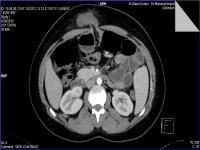

Medical imaging is an important investigative tool will help doctors to reach for the diagnosis of certain diseases, and the the advanced and high-quality imaging technologies are an important factor in maintaining the health of patients and accurate diagnosis of pathological lesions.